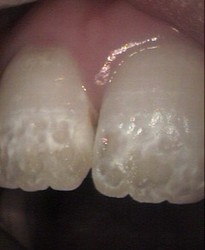

Brown spots on permanent front teeth micro abrasion

direct composite veneers